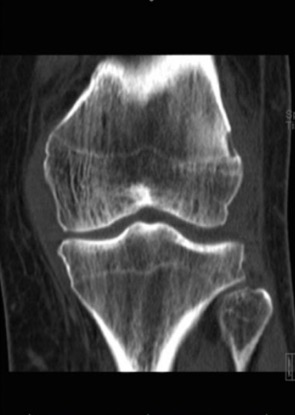

Możliwe do uzyskania obrazy diagnostyczne stawu kolanowego .

TK